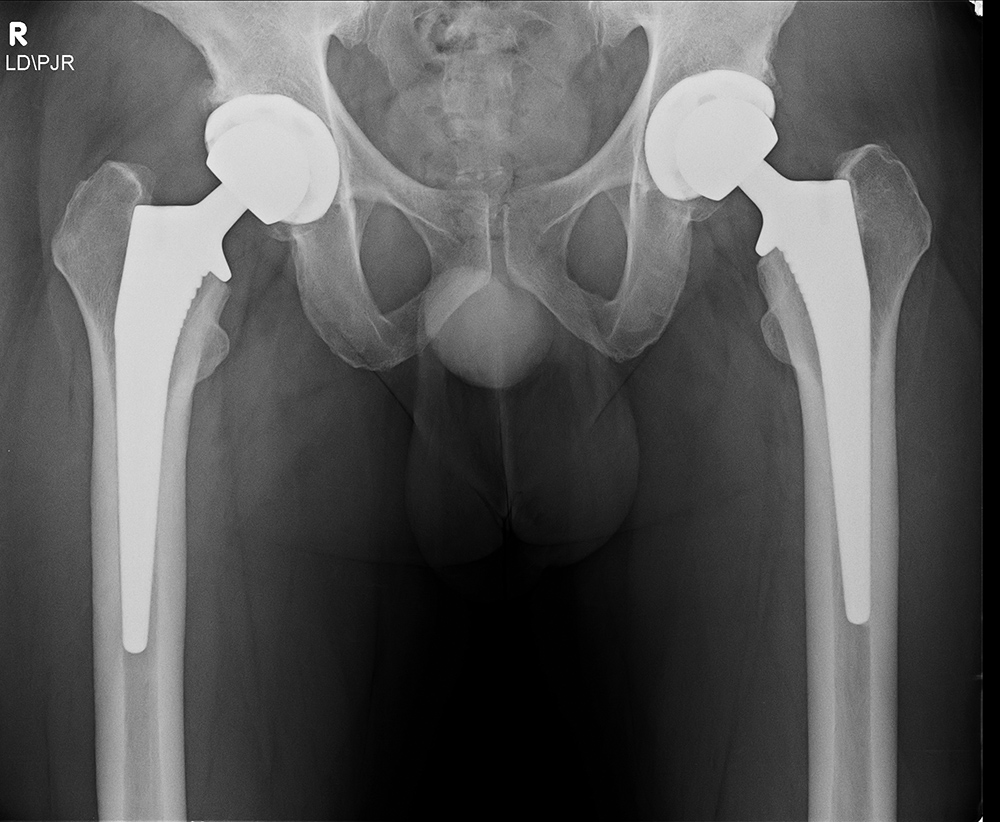

Total hip arthroplasty (THA) is the most common total hip replacement. It uses two components, a stemmed femoral component with a prosthetic femoral head and a prosthetic acetabular component (figure: modular total hip arthroplasty; figure: bilateral total hip arthroplasty). In 2011 there were 306,000 total hip replacements which is only second to 645,062 total knee replacements (AAOS). There were also estimated to be 105,509 partial hip replacements.

For patients younger than 65 with a normal life expectancy and adequate bone mass, cementless femoral stems are preferred (figure: bilateral total hip arthroplasty in 38 year-old man). It is possible that a femoral stem which has become well ingrown will not require revision, even if the acetabular component, and the articulating femoral head may need revision in the future. However, as in most cases with orthopedic surgery, the choice of components and the use of cemented or cementless femoral component depends on the surgeon's preference and experience. With any type of joint replacement, there is concern for its longevity and the need for ultimate revision or complete replacement. Revision surgery is usually not easy and may not have good results. Therefore, joint replacement is avoided as much as possible in younger patients and put off as long as is reasonable.

Bilateral total hip arthroplasty (THA) |

38 year old man with bilateral THA for advanced osteoarthritis. |

| Bilateral total hip arthroplasty (THA) |

| 38 year old man with bilateral THA for advanced osteoarthritis. The acetabular cup on an AP view of the pelvis should have 30-50 degrees of lateral inclination, which is measured as the angle between the rim of the acetabular cup and a line tangential to the ischial tuberosities. |

38 year old man with bilateral THA for advanced osteoarthritis. On a true cross-table lateral view of the hip there is normally 5-25 degrees of anteversion which is measured as the angle between the rim of the acetabular cup and a line drawn perpendicular to the horizontal surface. |

38 year old man with bilateral THA for advanced osteoarthritis. The distances from a line (C) between the centers of the femoral heads to a line running tangential to the ischial tuberosities (A) should be equal on each side, and the distances between the centers of the femoral heads to a line (B) running tangential to the tops of the greater trochanters should be equal on each side. Lines A, B, C should be parallel. |

38 year old man with bilateral THA for advanced osteoarthritis. The distances from the centers of the femoral heads on each side to the tops of the acetabular tear drops should be equal. |